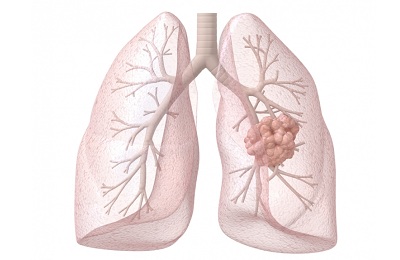

Доброкачественные образования появляются из обычных, похожих на здоровые, клеток. В них образуется псевдокапсула, а окружающие ткани атрофируются.

Метастазы данный вид опухолей не образует. Доброкачественные опухоли появляются в большинстве своем у мужчин и женщин до 45 лет, а общий в процентном соотношении они составляют около 7-10% от всей совокупности всех возможных новообразований в легких.

Доброкачественные опухоли бронхов происходят от клеток, которые схожи в своем строении со здоровыми клетками. Эти образования медленно растут, не разрушают соседние клетки и не инфильтруют.

- Периферические опухоли более распространенные, нежели центральные, они локализуются в равной степени в обоих легких, они склонны образовываться из бронхов и располагающихся рядом с ними многочисленных тканей. Наиболее часто встречающийся тип опухолей.